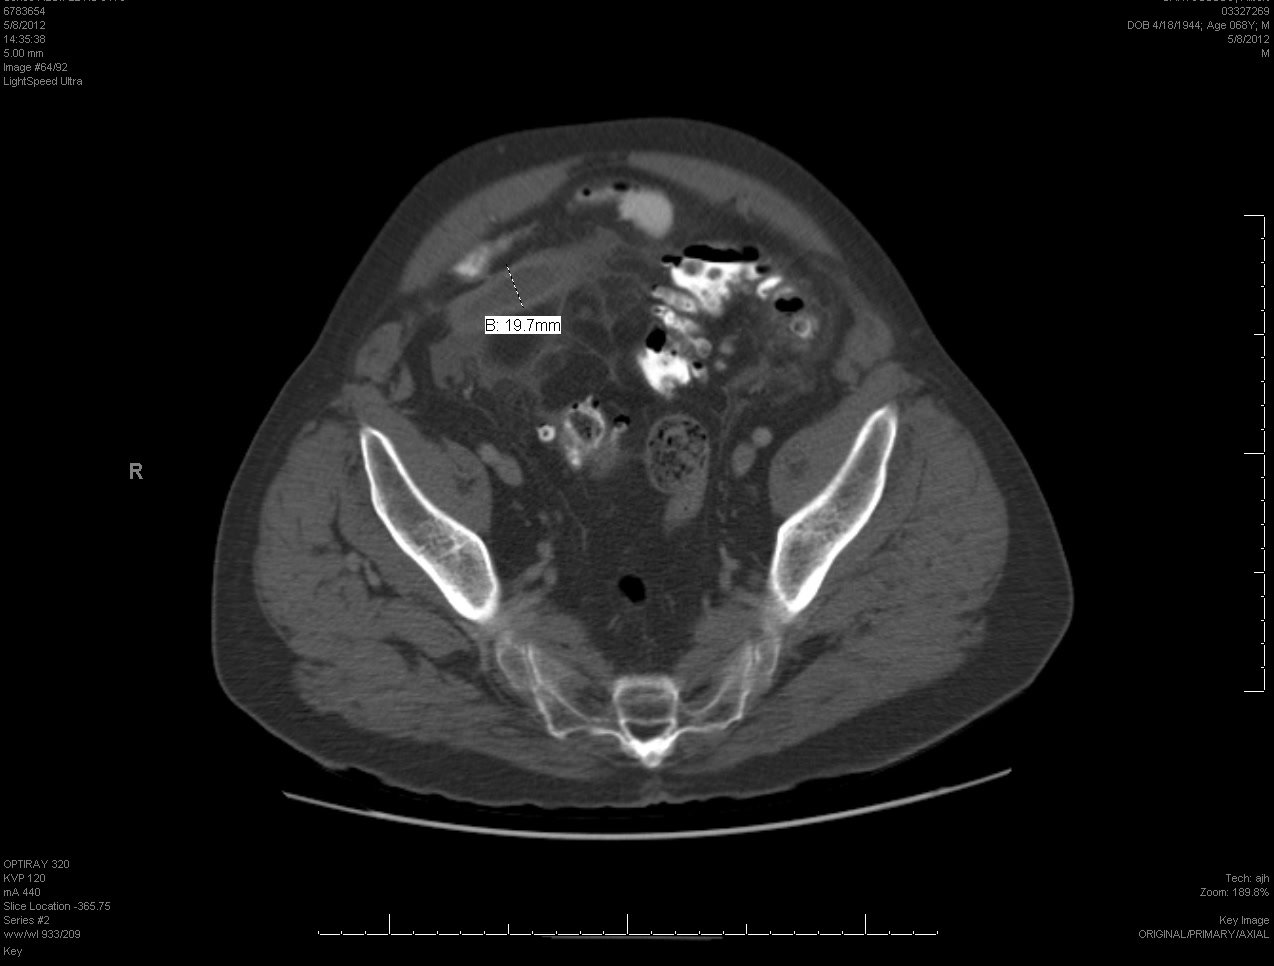

24yo F G2P1011 with hx of kidney stones presents complaining of right sided abdominal pain. The goals for this case are to recognize potential causes of right sided abdominal pain and the utility of using bedside US to narrow your differential and ultimately obtain your diagnosis.